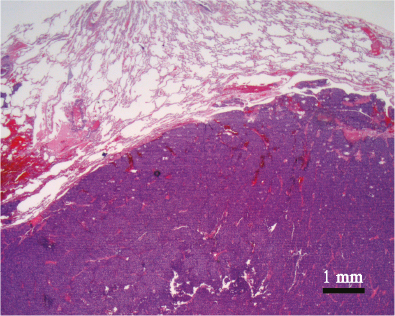

Fig 1

Figure 1. Blue cell tumor. The microphotograph depicts a resection specimen of the lung showing a “round” blue cell tumor involving the right lower half portion of the picture (dark blue area). The tumor is well demarcated and the intensity of the tumor cells is identifiable easily comparing to the alveolar parenchyma of the lung of the left upper half of the picture. The “roundness” of the tumor cells with round-ovoid contour is not appreciable at this magnification, but is better identifiable in figure 2 (Hematoxylin and Eosin staining x 12.5 original magnification).